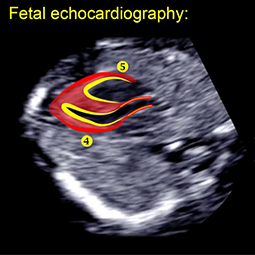

مهارت و توانایی استفاده از تمام روش های اکوکاردیوگرافی شامل دو بعدی، حالت M، موج پالس، موج پیوسته و نقشه جریان رنگ داپلر در تشخیص و ارزیابی وضعیت قلبی عروقی طبیعی و غیرطبیعی جنین را دارند.

1.- اکوکاردیوگرافی 2 بعدی (دو بعدی): به شما امکان می دهد آناتومی قلب، عروق و حرکات آن را در زمان واقعی مشاهده کنید. با این تکنیک، پزشک اندازه گیری ها و ارزیابی حرکات قلب را انجام می دهد.

اکوکاردیوگرافی دو بعدی (دو بعدی). این روش جهت "دیدن" ساختارهای واقعی و حرکت ساختارهای قلب به کاربرده می شود. یک نمای اکو دو بعدی به شکل مخروطی روی مانیتور ظاهر می شود و می توان حرکت لحظه ای ساختارهای قلب را مشاهده کرد. این پزشک را قادر می سازد تا ساختارهای مختلف قلب را در محل کار ببیند و آنها را ارزیابی کند.

اکوکاردیوگرافی 2 بعدی (2 بعدی)

این تکنیک برای "دیدن" ساختارهای واقعی و حرکت ساختارهای قلب استفاده می شود. این به پزشک شما امکان می دهد تا ساختارهای مختلف قلب را در محل کار ببیند و ارزیابی کند. اکوکاردیوگرافی داپلر: این تکنیک برای اندازه گیری و ارزیابی جریان خون در حفره ها و دریچه های قلب استفاده می شود. مقدار خونی که با هر ضربان خارج می شود، نشانه ای از عملکرد قلب است.